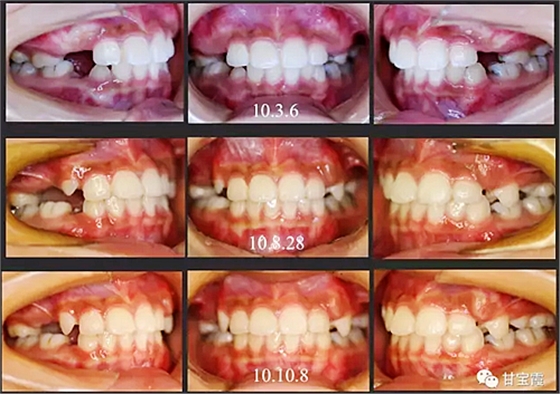

經(jīng)過我臨床檢查和X線的診斷,決定早期干預(yù),每三個(gè)月定期復(fù)診檢查一次,并拔掉了幾個(gè)乳牙和四個(gè)恒牙,正畸專業(yè)叫序列拔牙。

經(jīng)過三年零九個(gè)月的看護(hù),最終戴上了固定矯治器,但是大家不難發(fā)現(xiàn),孩子的牙齒已經(jīng)排齊,上下中線也基本對齊,面型也好看多了,這樣矯正就變得簡單,療程自然縮短,孩子也不遭罪了。